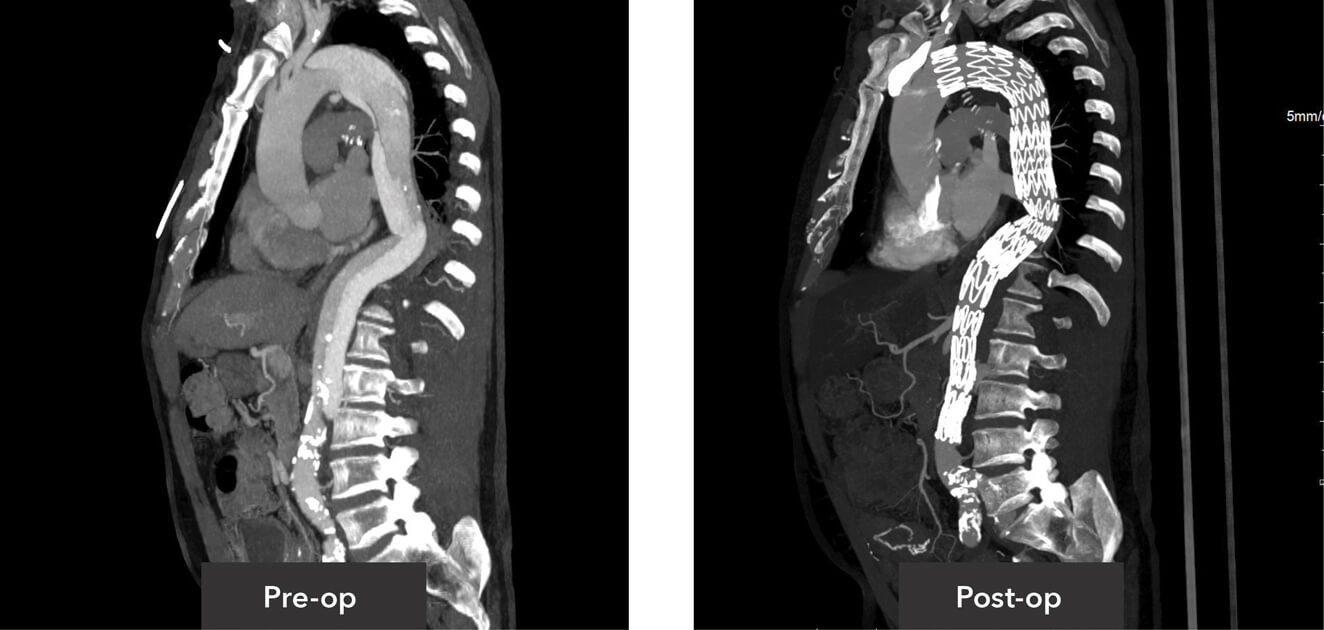

Sagittal view pre-op/post-op CT imaging